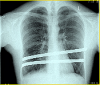

Meine Bilder